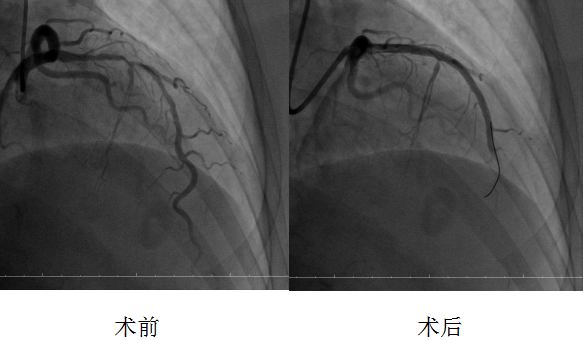

面对这一棘手病例,多学科团队分工协作、精准施策:肾病内科团队精准评估患者肾功能,制定个体化围手术期透析方案,严密监测电解质及内环境稳定,为手术筑牢安全基础;心内科团队则聚焦冠脉病变的精确评估与手术策略制定,经术前检查明确,左前降支近中段重度狭窄伴重度钙化是患者胸痛的核心病因,也是手术治疗需要攻克的关键难题。经多学科团队充分研讨,鉴于传统介入手段难以处理如此严重的钙化病变,最终决定采用先进的冠状动脉腔内斑块旋磨技术,联合球囊扩张及支架植入术的治疗方案。

10月17日,在介入科的全力配合下,刘波主任主导开展手术。手术团队运用直径仅1.5毫米的高速旋磨头,以每分钟15万转的转速精准“打磨”血管内钙化病灶,三次旋磨成功打通病变通路,随后顺利为患者串联植入两枚药物支架并以球囊行后扩张。为确保手术效果,团队还通过血管内超声检查精准评估支架贴壁情况,对支架近端进行补充后扩张。复查造影显示,支架释放满意,血管狭窄解除,血流恢复正常。术后1小时即实施双泵透析,有效降低造影剂对肾脏的影响,保障了患者心肾功能稳定。经过后续规范治疗,患者恢复良好,现已顺利出院。